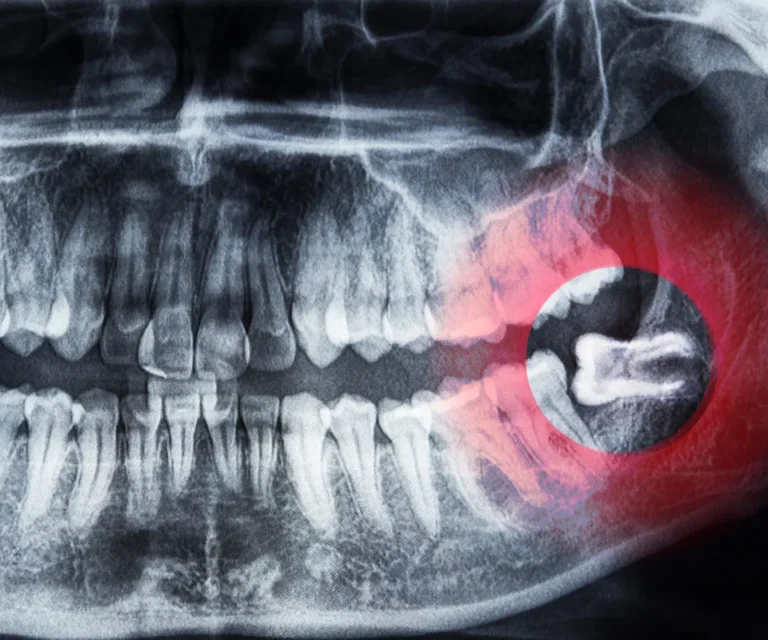

Diagnosis

A quick but thorough exam, including X-rays if necessary.

Wisdom Tooth Infection Emergencies

Wisdom teeth are especially prone to infection due to their position in the back of your mouth, making them harder to clean. Common signs of a wisdom tooth infection include:

Yes, especially with impacted wisdom teeth. Because they are difficult to clean, they’re at higher risk for infection, inflammation, and abscesses. Prompt wisdom tooth extraction is often recommended.